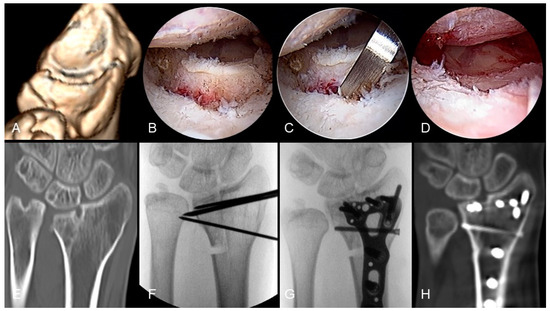

First, an inside-out osteotomy was performed: using 3-4 mm straight and curved osteotomes, the step-offs or gaps of the articular surface were gradually pried open. Then, through a volar extended FCR approach, the extra-articular malunion scarring was thoroughly released, followed by an outside-in osteotomy; this could be achieved by using an osteotome with a guiding needle inserted from the joint capsule or an aiming guide with K-wires to connect the intra-articular and extra-articular osteotomies [30]. The goal was to independently mobilize each malunited intra-articular fragment. Subsequently, under the scope, these particular fragments were reduced and transfixed with K-wires and then a locking plate was used for the definitive fixation of both intra-articular and extra-articular malunions. After completing the bony procedure, if concurrent injuries to the TFCC, scapholunate interosseous ligament, or lunotriquetral interosseous ligament are identified, corresponding repair or reconstruction surgeries can be performed simultaneously. Figure 3 shows the progressive steps involved in arthroscope-assisted correction for an intra-articular distal radius malunion. The process begins with a preoperative assessment of the articular step-off from a 3D CT reconstruction, with carpal bones subtracted (Figure 3A), and further verification through the arthroscope (Figure 3B). An inside-out osteotomy is then performed (Figure 3C), followed by the reduction of the intra-articular malunion (Figure 3D). The preoperative condition is also shown in a CT coronal view (Figure 3E). Temporary K-wire fixation stabilizes the reduced articular surface (Figure 3F), and definitive fixation along with length correction is achieved through a distal radius locking plate and additional ulna shortening osteotomy (Figure 3G). An 8-month follow-up CT coronal view confirms the joint congruence and bony union of the corrective osteotomy (Figure 3H).

Figure 3. Arthroscope-assisted corrective osteotomy of intra-articular distal radius malunion: (A) preoperative articular step-off noted from 3D CT reconstruction with carpal bones subtraction; (B) articular step-off noted through arthroscope; (C) inside-out osteotomy; (D) reduction of intraarticular malunion; (E) preoperative CT coronal view; (F) temporary K-wires fixation of reduced articular surface; (G) definitive fixation and length correction with additional ulna shortening osteotomy; (H) follow-up CT coronal view 8 months later. Image courtesy of the corresponding author Chen-Yuan Yang, MD.